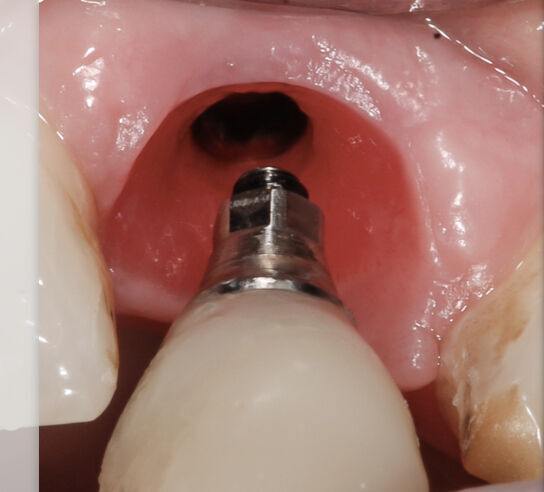

Restoring single tooth implants with the Straumann Implant system

Restoring Single Tooth Dental Implants